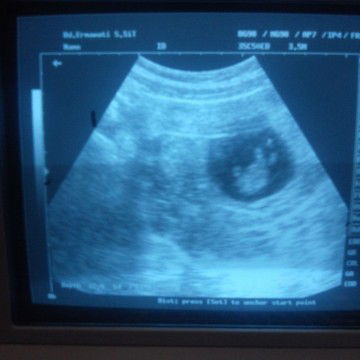

detak jantung bayi

Tadi saya usg bun, usia kandungan saya 10 week 5 day, udah kedengeran suara detak jantungnya, katanya 145 permenit, katanya klo detak jantungnya lebih dari 140 permenit kemungkinan anaknya cewek, dan anak saya yg pertama memang betul bun waktu hamil detak jantungnya diatas 140 permenit dan lahirnya cewek, kira kira ada gak ya bunda bunda yg sm pengalamannya kaya aku, karena cuma mau berbagi pengalaman aja, karena cowo atau cewek tentunya kita sebagai ortu gak pernah permasalahin ???